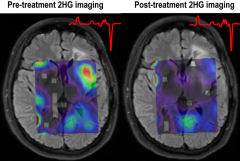

美国哈佛医学院新颖的成像方法揭示了针对 脑胶质瘤 的靶向治疗背后的机制,一种新颖的成像方法揭示了代谢物的减少,这可能有助于肿瘤的发生。 位于...

ML309作为IDH1突变的竞争性控制剂,与α-KG依赖酶竞争活性位点,降低胶质母细胞瘤中2-HG的水平。AG-221是IDH2的选择性小分子控制剂,2013年底一次进入临床试...